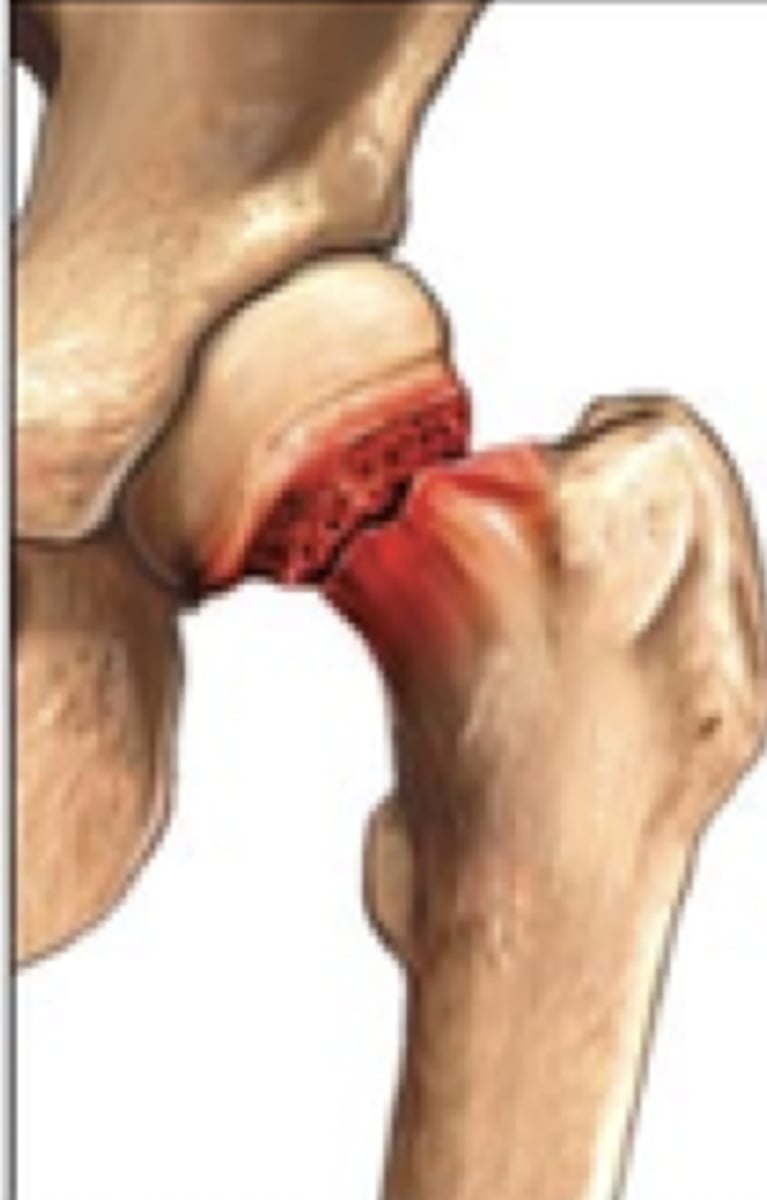

gardens I fx

gardens II fx

gardens III fx

gardens IV fx

intercapsular fx